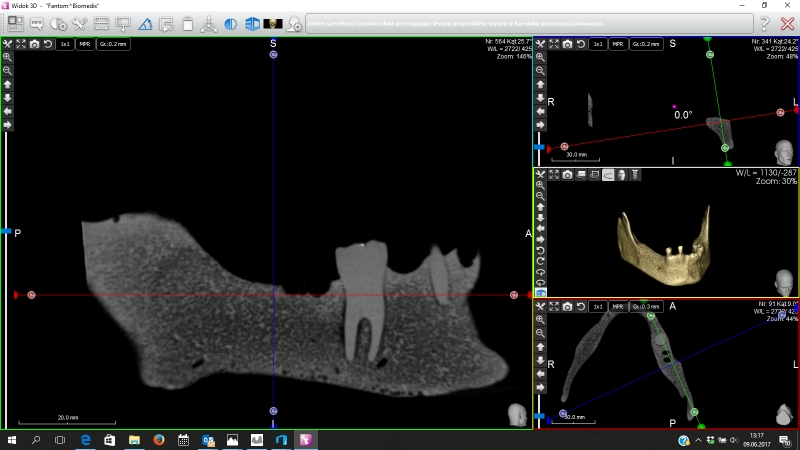

Oferujemy również szablony chirurgiczne przeznaczone do szkoleń z implantacji. Umożliwiają planowanie leczenia implantologicznego i przeprowadzenie szkoleń z wykorzystaniem plików CT, STL oraz druku 3D. Oferujemy nasze modele do szkoleń implantologicznych wraz z plikami DICOM i STL.

Pliki do wykonania szablonów można pobrać z naszej strony internetowej. Możemy je również dostarczyć wraz z modelami. Pliki te dostępne są dla modeli 10-1030, 10-3040, 10-3050, 10-5070,